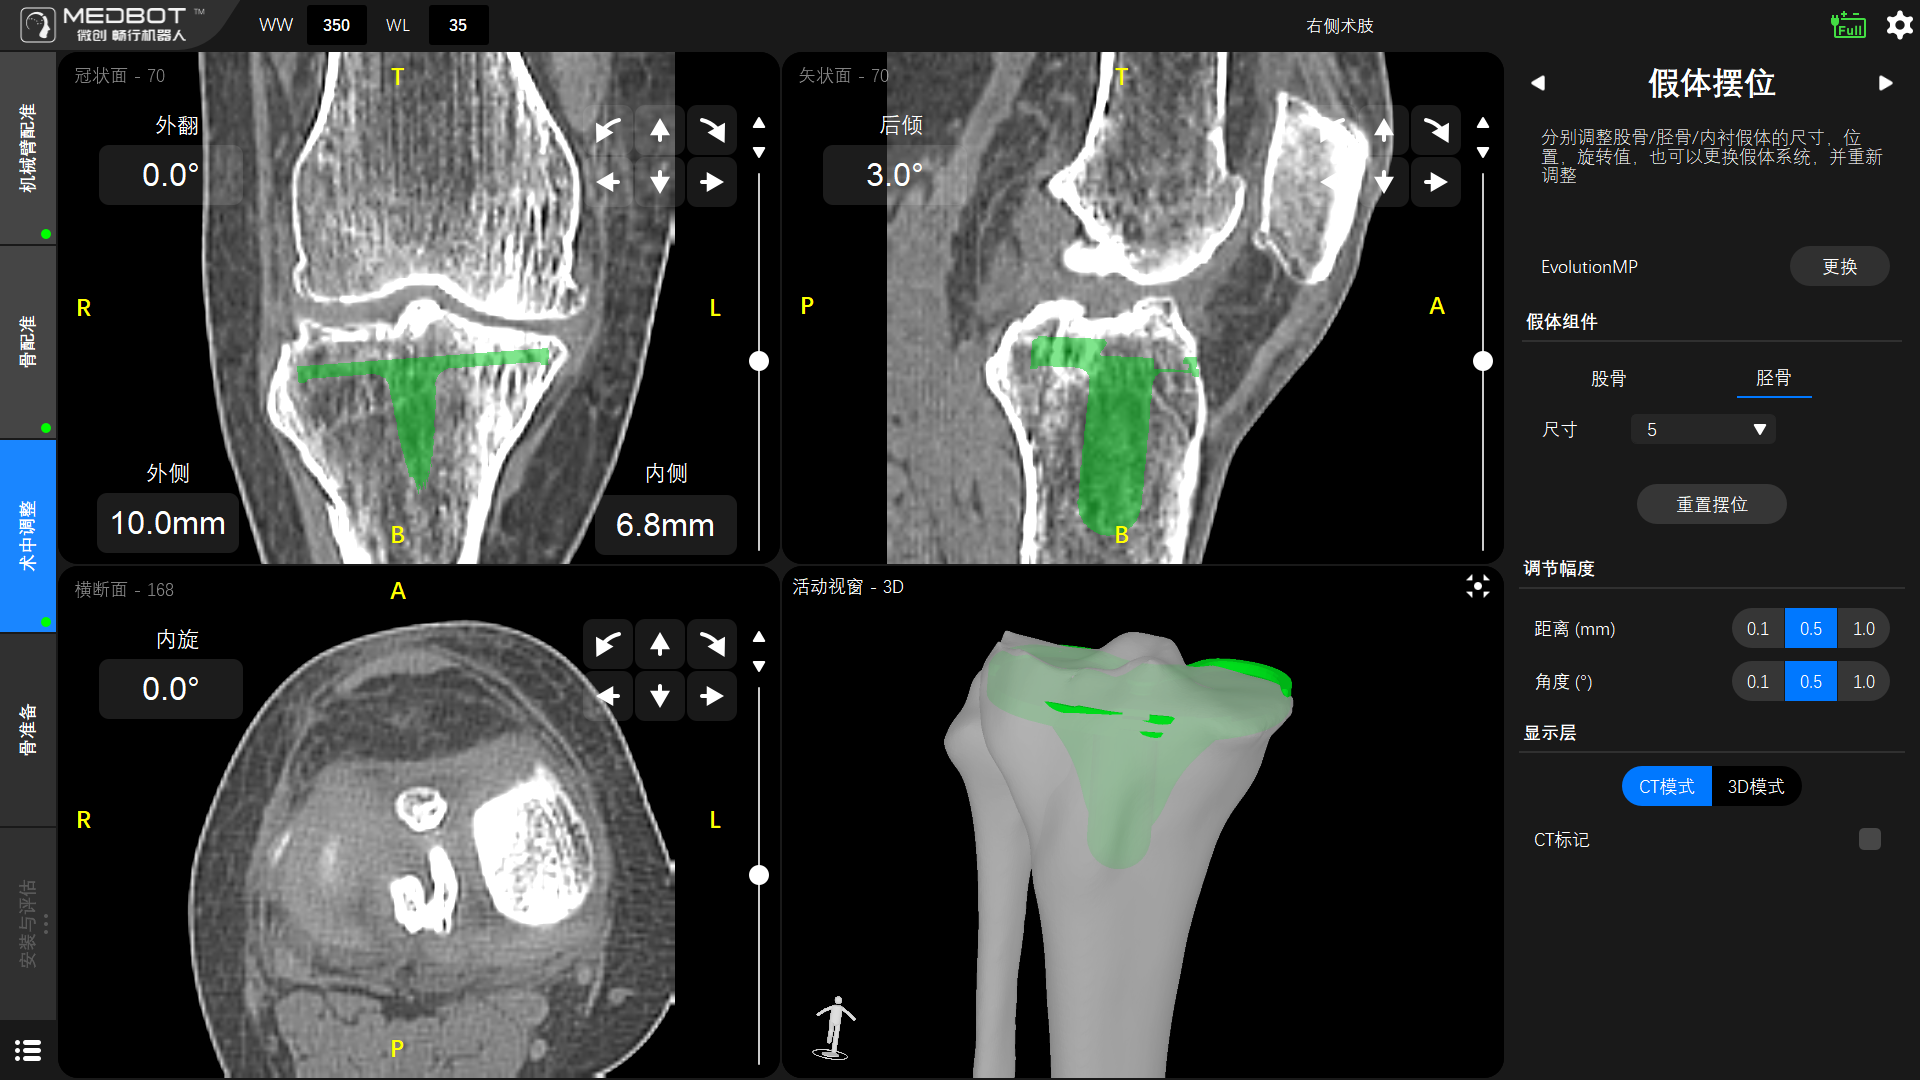

術(shù)前,薛勇主任和黎志超主任團(tuán)隊(duì)通過鴻鵠®機(jī)器人的規(guī)劃軟件為患者進(jìn)行了膝關(guān)節(jié)CT圖像的三維重建,制定符合患者生理解剖特征的個(gè)性化假體放置方案。

▲股骨假體擺位

▲脛骨假體擺位